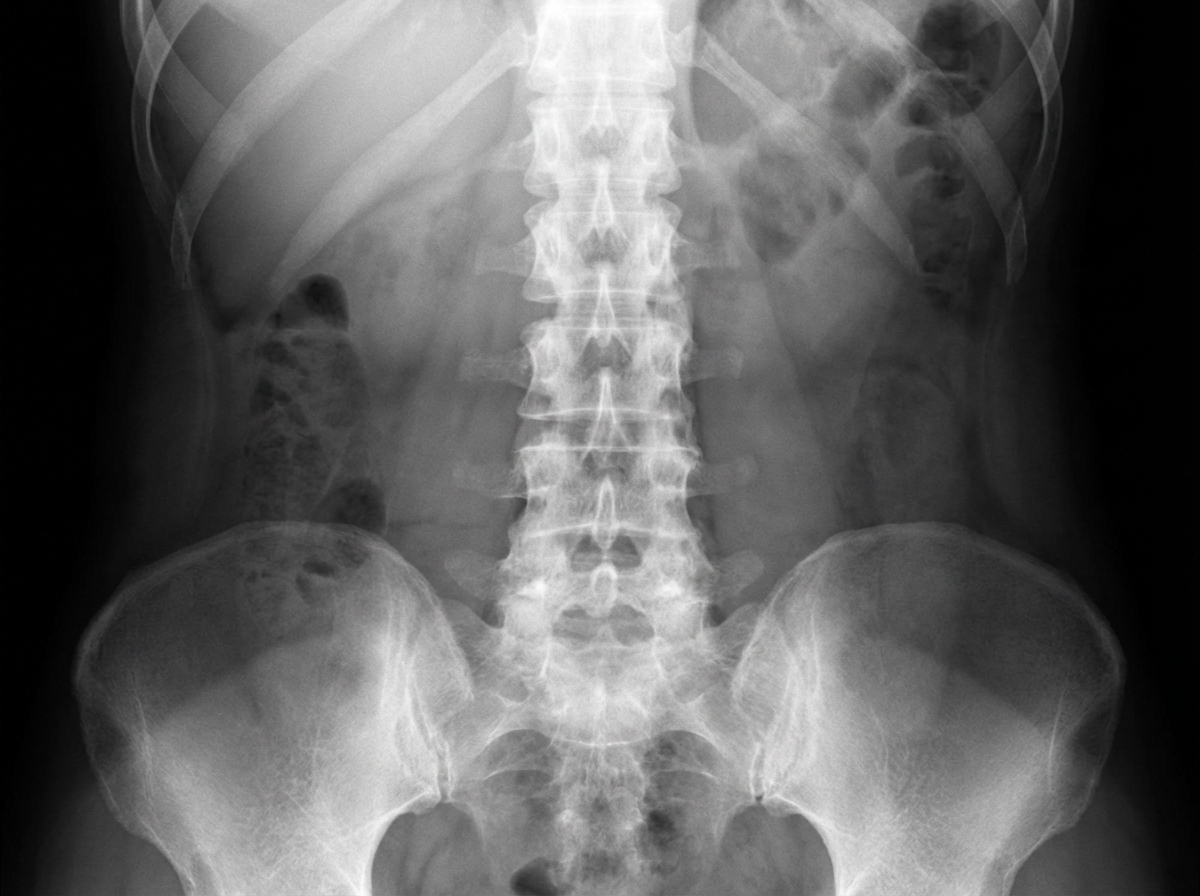

A 36-year-old man comes to the physician because of increasing back pain for the past 6 months. The pain is worse when he wakes up and improves throughout the day. He has problems bending forward. He has taken ibuprofen which resulted in limited relief. His only medication is a topical corticosteroid for two erythematous, itchy patches of the skin. His mother has rheumatoid arthritis. His temperature is 37.1°C (98.8°F), pulse is 75/min, respirations are 14/min, and blood pressure is 126/82 mmHg. Examination shows a limited spinal flexion. He has two patches with erythematous papules on his right forearm. He has tenderness on percussion of his sacroiliac joints. An x-ray of his spine is shown. Which of the following is most likely to improve mobility in this patient?